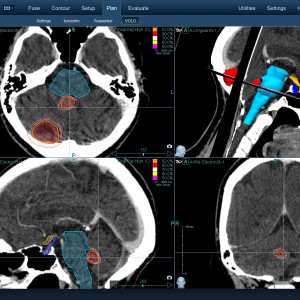

Στις παρακάτω φωτογραφίες θα δείτε παραδείγματα πλάνων θεραπείας καρκινικών όγκων με CyberKnife. Παρατηρήστε πόσο κοντά στους υγιείς ιστούς βρίσκονται οι καρκινικοί όγκοι που χρειάζεται να ακτινοβοληθούν. Μόνο με το CyberKnife και το προσωπικό πλάνο θεραπείας, μπορούν να ακτινοβοληθούν οι όγκοι χωρίς να πληγούν οι παρακείμενοι υγιείς ιστοί.

Μόνο με το CyberKnife και την κατάλληλη σχεδίαση της θεραπείας από έμπειρο νευροχειρουργό, μπορεί να ακτινοβοληθούν οι όγκοι χωρίς να επηρεαστούν από την ακτινοβολία οι υγιείς ιστοί. Αυτό εξασφαλίζει τη μέγιστη δυνατή απόδοση της ακτινοχειρουργικής θεραπείας των όγκων.

Με κόκκινο χρώμα περιγράφεται η περιοχή του όγκου.

Με μπλε, κίτρινο και πράσινο χρώμα περιγράφονται οι υγιείς ιστοί που δεν πρέπει να ακτινοβοληθούν.

Παρατηρήστε πόσο κοντά βρίσκεται ο όγκος με τους υγιείς ιστούς.

Παρατηρήστε τις πάρα πολλές δέσμες του CynerKnife που ακτινοβολούν τους όγκους από διαφορετικές γωνίες ώστε να μην προσβληθούν από την ακτινοβολία οι υγιείς ιστούς.